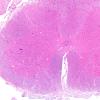

PERIPHERAL NEUROPATHY

7A GUILLAIN-BARRE SYNDROME (GBS) (5)